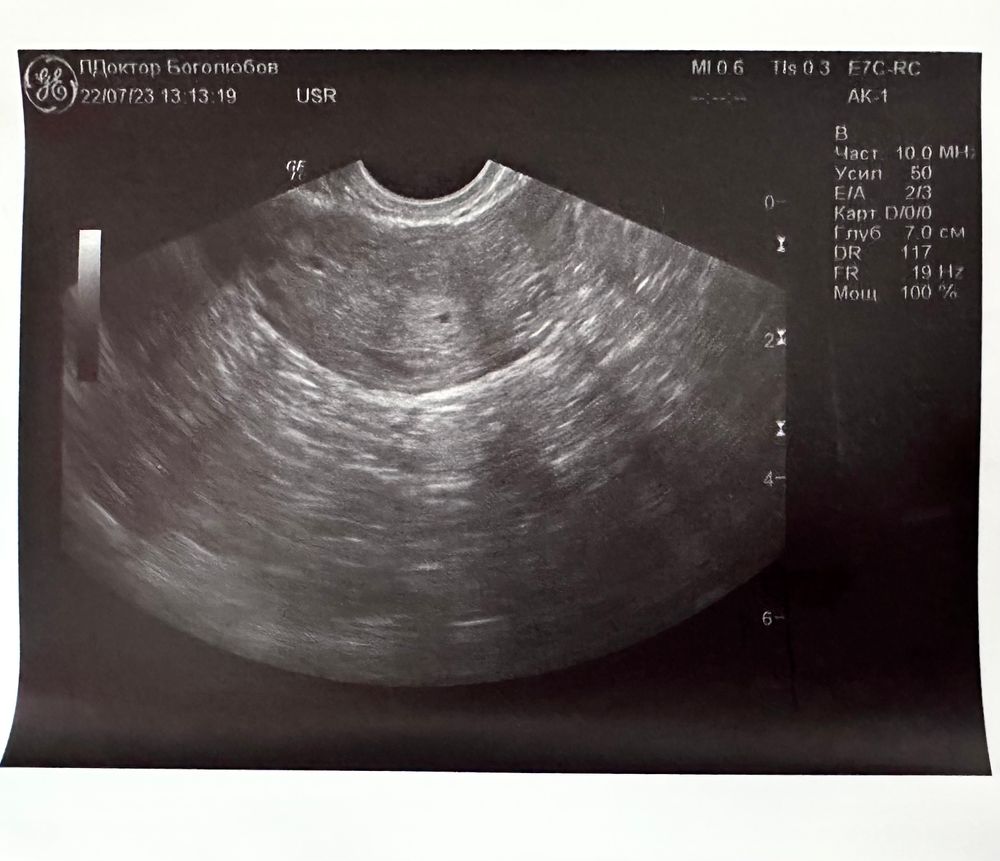

С утра сходила к врачу, нашли бусинку! Целых 2 мм 🥹

Тесты делать перестала, но хгч сдала. Посмотрим, что покажет, с тем условием, что 19.07 было 40 мМЕ, а сегодня уже узи показало 🤷🏻♀️

У меня на 18 дпо ХГЧ был 557,на 19 дпо увидели ПЯ 1,5 мм